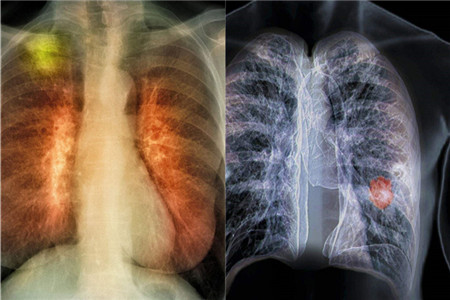

我们生活在当下时代,不得不说是幸运与不幸的结合。之所以幸运是因为经济快速发展,人们已经摆脱了基本的物质生活需求。不幸是因为环境遭到了破坏,长期生活在劣质环境中,难免会患上肺癌等各种病症。那么,怎样预防肺癌发生呢?